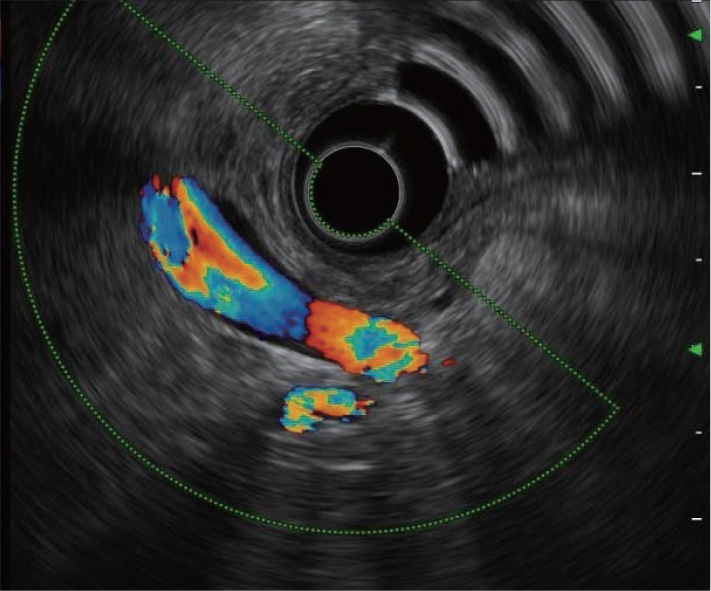

Doppler function

The Doppler function detects ultrasound signals from blood flows and converts them into images.

COLOR FLOW

Blood flow and velocity are displayed in color.

H-FLOW

Direction and amount of blood flow are displayed in color. Color smear is minimal. This is useful for detection of microvessels.